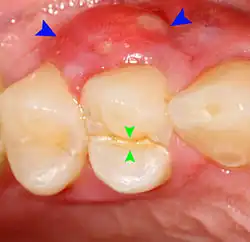

Lateral periodontal abscess (blue arrows) due to a fracture (green arrows)

A periodontal abscess (lateral abscess) is a collection of pus that forms in the gingival crevices, usually as a result of chronic periodontitis where the pockets are pathologically deepened greater than 3mm. A healthy gingival pocket will contain bacteria and some calculus kept in check by the immune system. As the pocket deepens, the balance is disrupted, and an acute inflammatory response results, forming pus. The debris and swelling then disrupt the normal flow of fluids into and out of the pocket, rapidly accelerating the inflammatory cycle. Larger pockets also have a greater likelihood of collecting food debris, creating additional sources of infection.[21]: 443

Periodontal abscesses are less common than apical abscesses, but are still frequent. The key difference between the two is that the pulp of the tooth tends to be alive, and will respond normally to pulp tests. However, an untreated periodontal abscess may still cause the pulp to die if it reaches the tooth apex in a periodontic-endodontic lesion. A periodontal abscess can occur as the result of tooth fracture, food packing into a periodontal pocket (with poorly shaped fillings), calculus build-up, and lowered immune responses (such as in diabetes). Periodontal abscess can also occur after periodontal scaling, which causes the gums to tighten around the teeth and trap debris in the pocket.[21]: 444–445  Toothache caused by a periodontal abscess is generally deep and throbbing. The oral mucosa covering an early periodontal abscess appears erythematous (red), swollen, shiny, and painful to touch.[22]

A variant of the periodontal abscess is the gingival abscess, which is limited to the gingival margin, has a quicker onset, and is typically caused by trauma from items such as a fishbone, toothpick, or toothbrush, rather than chronic periodontitis.[21]: 446–447  The treatment of a periodontal abscess is similar to the management of dental abscesses in general (see: Treatment). However, since the tooth is typically alive, there is no difficulty in accessing the source of infection and, therefore, antibiotics are more routinely used in conjunction with scaling and root planing.[23] The occurrence of a periodontal abscess usually indicates advanced periodontal disease, which requires correct management to prevent recurrent abscesses, including daily cleaning below the gumline to prevent the buildup of subgingival plaque and calculus.